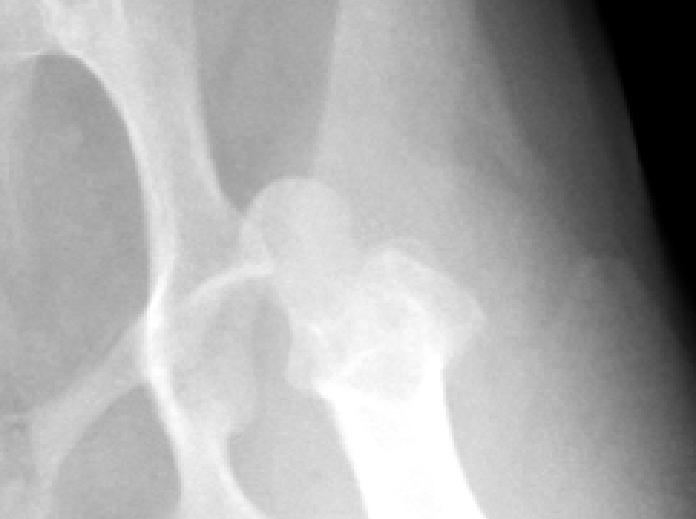

股関節脱臼

股関節は骨盤と大腿骨をつなげる関節です。大腿骨頭という円形の骨端が骨盤の寛骨臼という凹みにぴったり収まって機能する関節です。

この股関節が転倒や転落、交通事故など大きな力が加わることにより外れる状態を股関節脱臼と言います。犬の場合犬種によって元々外れやすい(関節が緩い)ことがあります。治療は外れたものを戻すことが基本となり様々な治療がありますが、再発やその都度強い痛みや跛行・接地不全を起こすこともあり骨頭を切除し歩様を改善させる治療などもあります。

実際の症例

12歳のウエスティー リンちゃん。

雪道を散歩中に突然腰が落ちるようになり『キャン』と鳴いた後から左後肢が着かなくなり来院されました。

• レントゲン写真1

• レントゲン写真2

レントゲンで左後肢の脱臼所見が認められました。麻酔下で非観血的に関節を戻し包帯で固定を行いましたが、数日で再脱臼を起こしてしまいました。飼い主さまと幾つかの治療プランや今後の経過プランを相談し大腿骨頭切除術を行うことにしました。